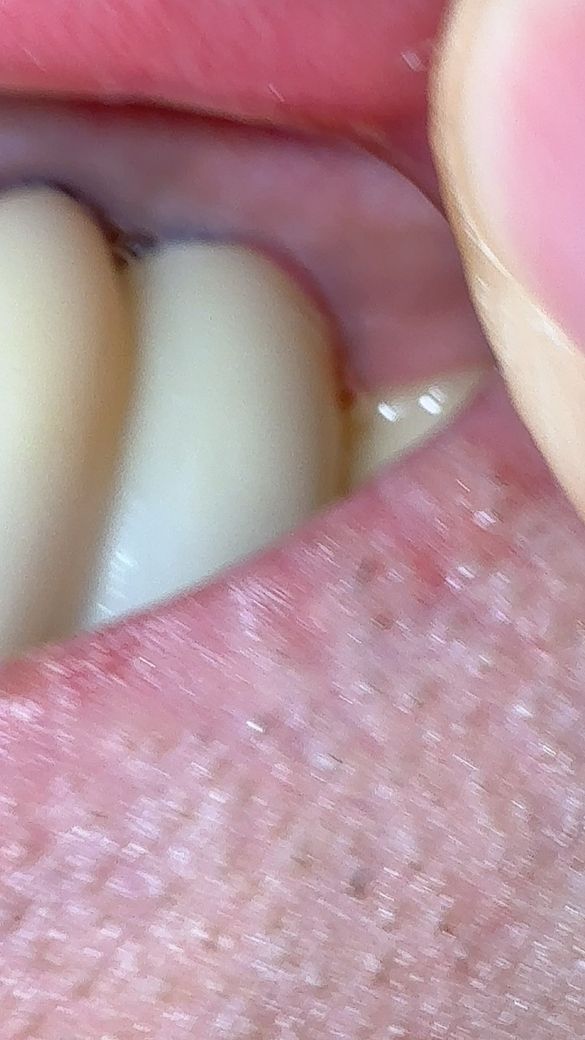

질문으로는 파노라마 사진에서 왼쪽의 상악 보철물의 세번째 잇몸입니다

1,2번째 사진에서 보시다시피 경계면(?)이 붉은 상태인지 어림잡아 3주가량 되었는데

• 1번 째 사진

사진으로보이는 붉은색은 과도한 자극으로 잇몸에 손상이 가해졌을 가능성이 높아 보입니다.